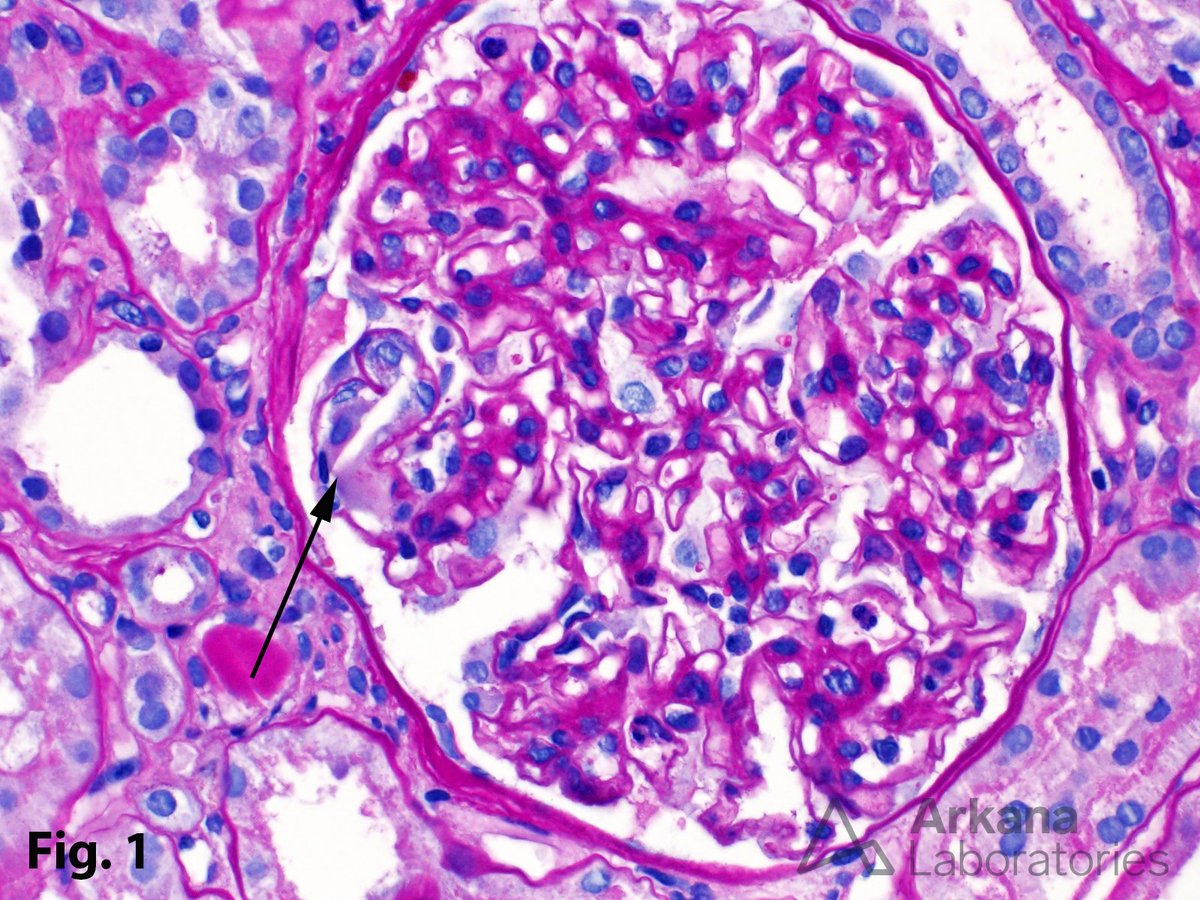

AJKD Atlas of Renal Pathology: Crystalglobulin-Induced Nephropathy https://t.co/TyG5KPwziJ (FREE) @podocytes @AlpersCharles @AgnesFogo #RenalPath Image: Large bright eosinophilic crystals within glomerular capillaries (arrow, Jones silver stain)